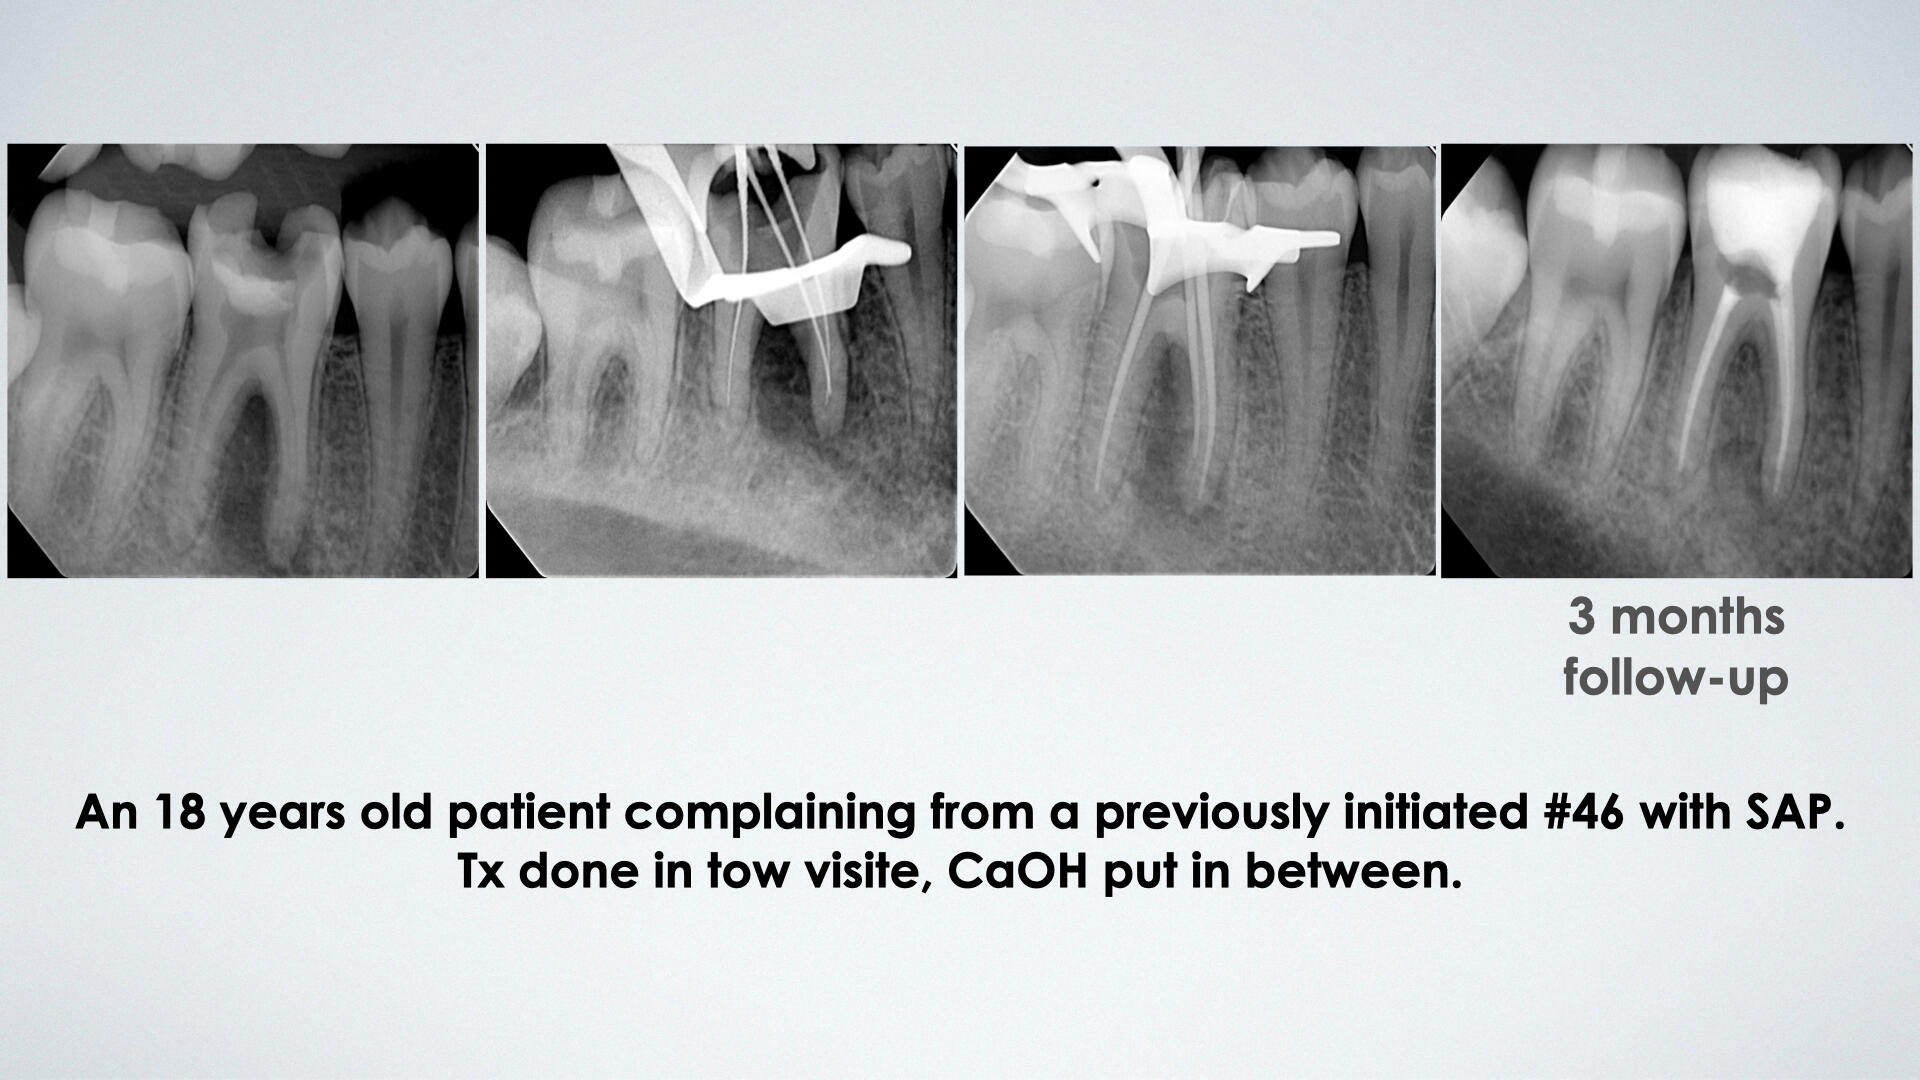

During my internship term, I have worked on 400+ different patients with a variety of cases. Portfolio includes esthetic, direct restoration, RCT and prothodintic cases.